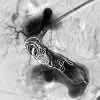

- Services: Embolization, chemoembolization, Yttrium-90 (90Y) radioembolization, microwave ablation, cryoablation, alcohol ablation, biopsies

- Services: Angiography, embolization